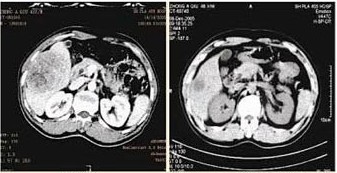

效果:经过一个疗程的治疗后复查,CT显示瘤体明显缩小,腹水全部消失。疼痛症状有效缓解,食欲增强,体重略有增加,精神状况明显好转,生活质量显著提高,生活可自理。2014年5月再次到医院复查,身体恢复良好,可像正常人一样生活。

治疗前后对比图